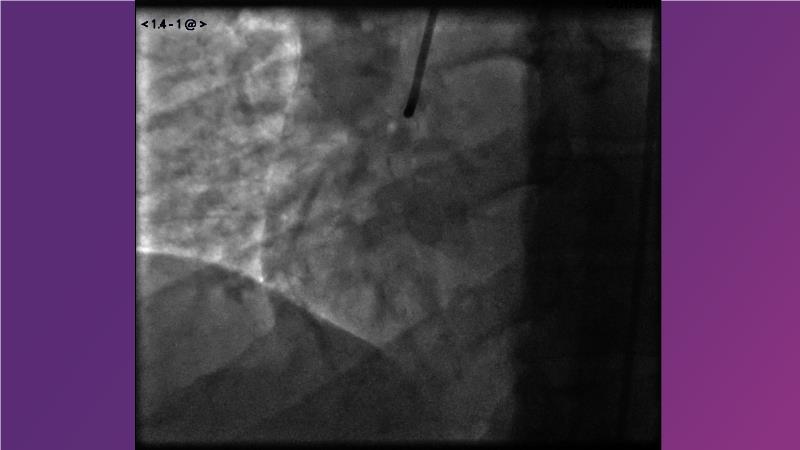

- To learn from the real world registries and complex cases to understand the practical implications and potential of the device in diverse patient population